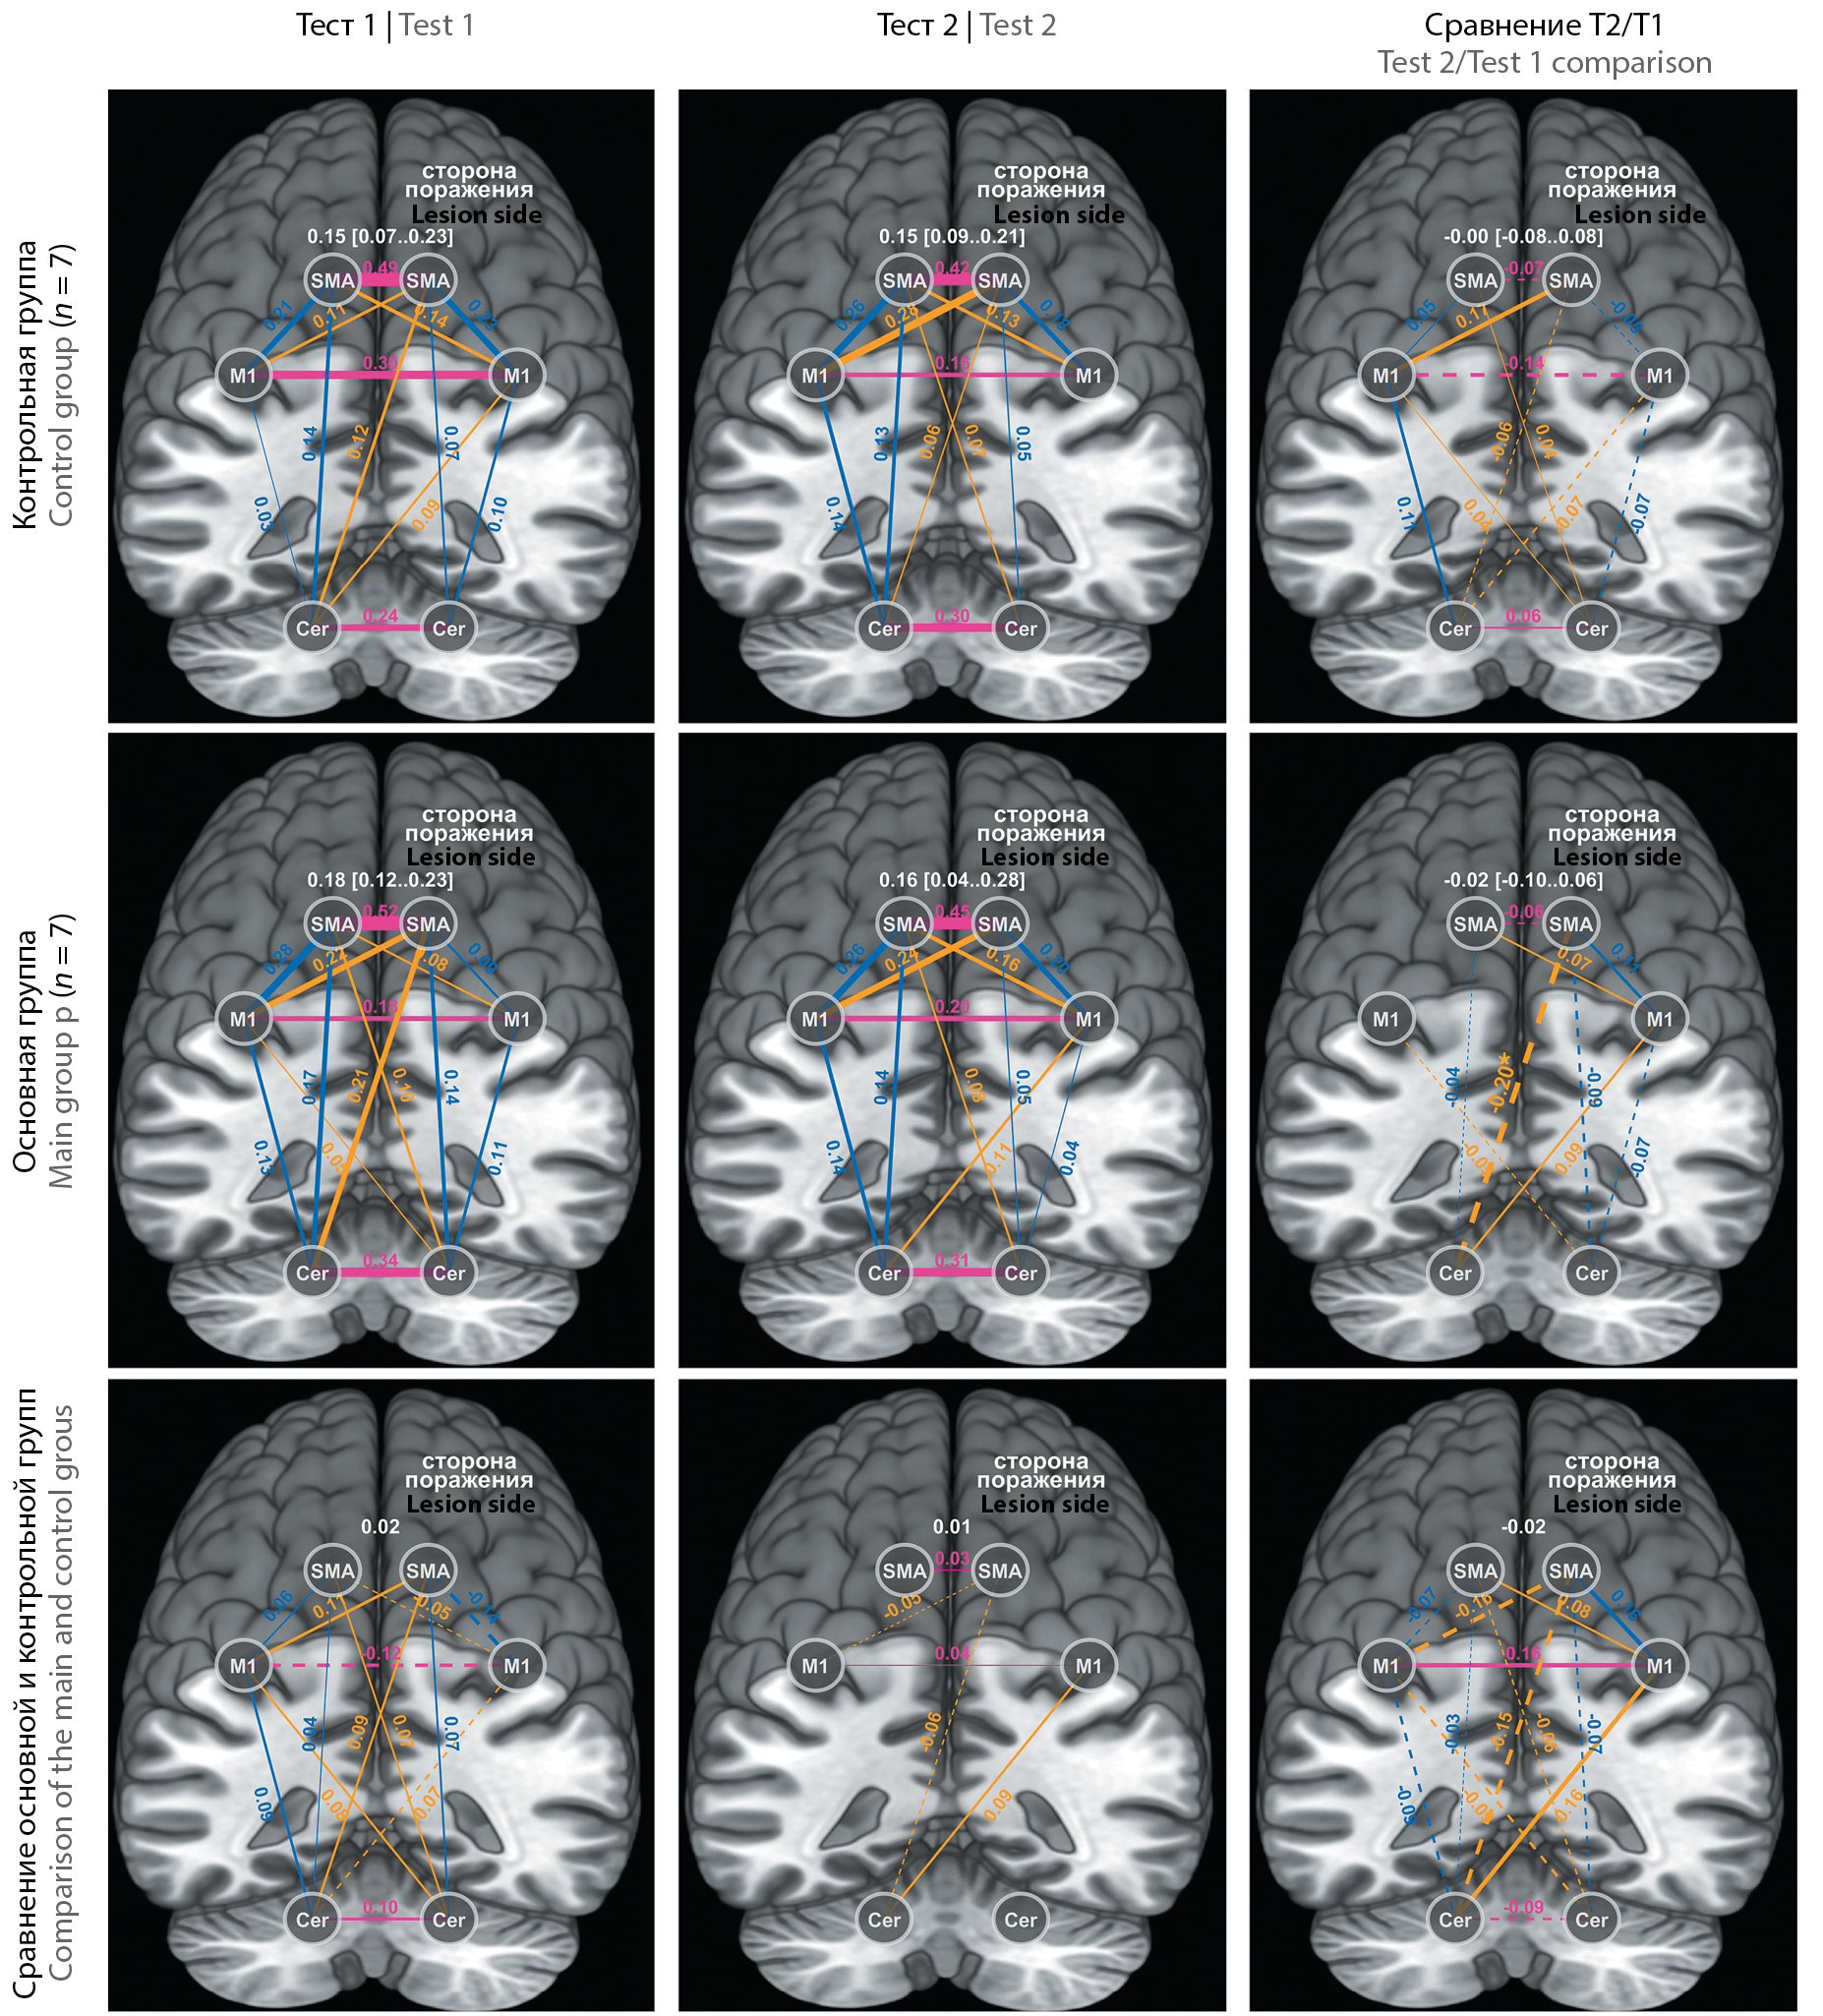

До лечения (тест 1) моторная сеть в состоянии покоя (фМРТ покоя) характеризовалась средней внутрисетевой связностью 0,18 в основной группе и 0,15 — в контрольной (p > 0,05). Исходных межгрупповых различий во взаимосвязях конкретных узлов внутри сети не было. К концу лечения (тест 2) достоверно ослабела связность SMA повреждённого полушария с противоположным Cer в основной группе; в остальном наблюдались лишь тренды (рисунок). В контрольной группе мы отметили тенденцию к ослаблению связности ипсилатеральной М1 с М1 противоположной стороны и с SMA — своей стороны (рисунок, верхний ряд). У пациентов основной группы взаимосвязь М1–М1 не изменилась; связность ипсилатеральной М1 стала сильнее с SMA обоих полушарий и с противоположным Cer (рисунок, средний ряд).

Матрицы ФС моторной сети у пациентов основной и контрольной групп до и после лечения. Регионы интереса обозначены белыми кругами; цветами выделены их взаимосвязи: розовым — межполушарные поперечные, оранжевым — межполушарные диагональные, синим — внутриполушарные; толщина линий между регионами схематично отражает силу функциональных связей (пунктиром показано ослабление связи); цифры над линиями обозначают коэффициент корреляции ρ. В правой и нижней частях рисунка приведены результаты сравнения ФС до и после курса лечения (внутри- и межгруппового соответственно). Цифры белого цвета над каждой матрицей отражают среднее значение внутрисетевой связности (или разницу её внутри и между группами — в правой и нижней частях рисунка соответственно), в квадратных скобках указан доверительный интервал для этого среднего с уровнем доверия 0,95. *p < 0,05 (тест Стьюдента)

FC matrices of motor networks in the main and the control groups prior to and after the treatment. The white circles designate the regions of interest, the colored lines indicate their connections. The rose lines represent interhemispheric

cross-lateral connections, the orange lines represent interhemispheric diagonal connections, and the blue lines represent intrahemispheric connections. The strength of the functional connections is proportional to the width of the lines, with weaker connections indicated by dotted lines. The correlation coefficient (ρ) is shown above the lines. The results of FC comparison before and after the treatment are presented on the right and on the lower panels, within and between the groups, respectively. Digits in white above each matrix reflect the mean value of the intranetwork connectivity or the difference in its level within or between the groups: on the right and on the lower panels, respectively. The confidence interval of 0.95 for this mean value is shown in the brackets. *p < 0.05 (using Student's t-test).

Клинико-сетевые корреляции

Корреляционный анализ показал прямую зависимость в тесте 2 для всех больных между силой межполушарной связности М1 и результатами FM-UE (ρ = 0,87; p < 0,005), ВВТ (ρ = 0,72; p < 0,01) и динамометрии (ρ = 0,69; p < 0,01). В тесте 1 сила взаимосвязи М1–М1 слабо коррелировала с ВВТ (ρ = 0,45; p < 0,05). Для связи SMA справа и Cer слева к завершению курса обнаружена обратная зависимость с результатами ВВТ и FM-UE (для обоих ρ = –0,44; p < 0,05).

В нашем исследовании межполушарная связность М1 в контрольной группе к концу курса физической реабилитации ослабла, в то время как в основной она не менялась или характеризовалась тенденцией к усилению. Одновременно в группе ИСМ укрепилась внутриполушарная связь М1–SMA на стороне инсульта; в контрольной группе такой тенденции не отмечено (рисунок). При этом результаты функциональных тестов (ВВТ, FM-UE и динамометрия) прямо коррелировали с силой межполушарной связи М1–М1.

Мозжечок участвует в моторном обучении и далее — в моторном контроле уже сформированного навыка [36]. Мы наблюдали укрепление взаимосвязи М1 повреждённого полушария с противоположным Cer у больных основной группы и ослабление ФС ипсилатеральной SMA с обоими полушариями Cer у всех больных (рисунок). В какой мере такие тенденции обусловливают успешность моторного обучения после инсульта, не вполне понятно, хотя мы выявили обратную корреляцию результатов функциональных тестов с силой связи SMA повреждённого полушария с противоположным Cer.